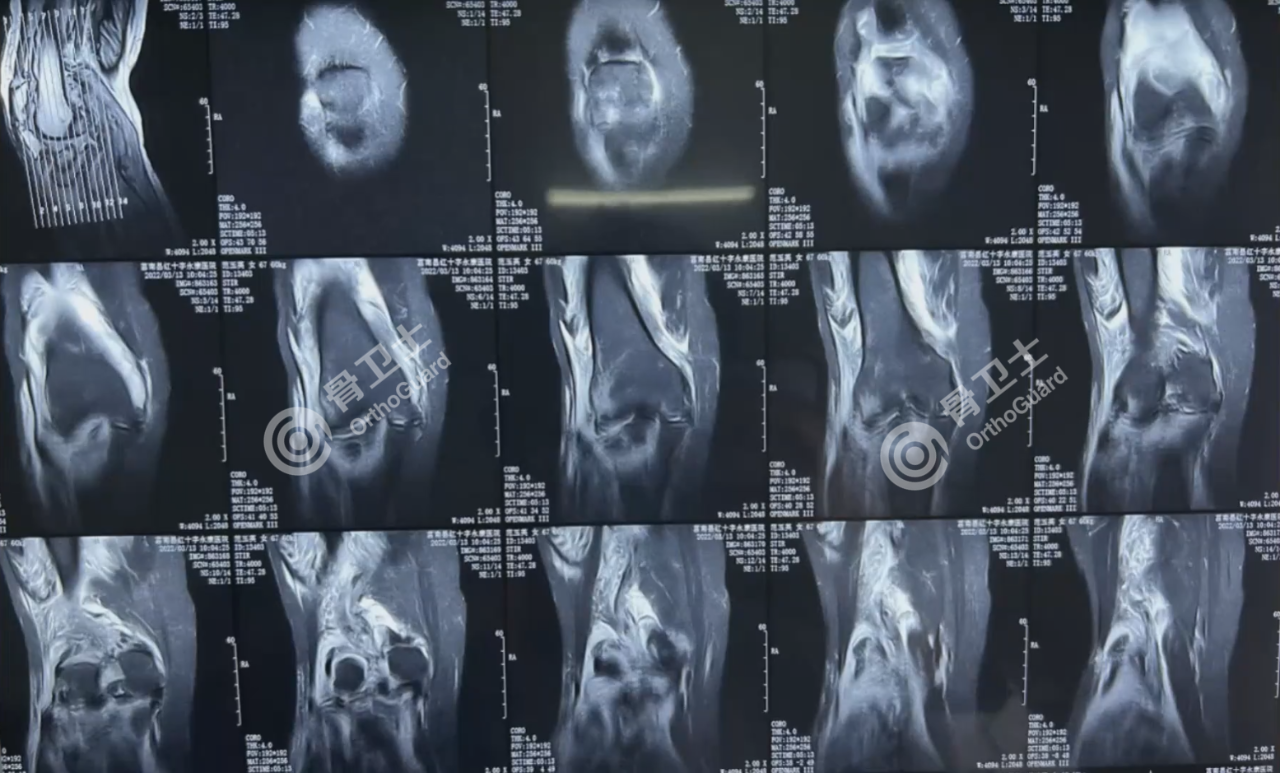

基本情况:女,67岁,因右膝部外伤后疼痛2小时入院。

查体:右膝关节肿胀明显,胫骨平台外侧压痛明显,扪及骨擦感及异常活动,膝关节因疼痛主动活动受限,足背动脉波动正常,下肢感觉、血运正常。

诊断:右胫骨平台闭合性骨折、右腓骨近端闭合性骨折。

治疗方案:计划右胫骨平台切开复位植骨内固定术,由于病人患肢肿胀明显,不利于即刻手术,可行右下肢石膏固定,抬高患肢,应用镇痛、消肿药物,待消肿后,适当时机实行手术。

▲患者影像资料

周乙雄教授和陈强副院长就患者治疗方案及术式选择进行探讨。周乙雄教授介绍了胫骨平台骨折的类型和处置方式。从胫骨平台骨折分型、麻醉方式选择、手术时机选择、切口的选择,植骨的处置以及术后康复方案给出建议。

周乙雄教授指出,该患者骨折部位前期肿胀严重,需检查凝血机制,必要时检查患侧下肢深静脉的B超,以排除血栓,若有深静脉血栓,需及时处理;如无血栓,待消肿后进行手术,术后12小时开始使用抗凝药,术后24小时开始循序渐进活动,避免血栓形成。手术需做好植骨准备;关于切口的选择,建议做正中偏外侧一点的,注意勿损伤腓总神经及其他神经血管。周乙雄教授指出,要做好术后患者的康复指导,尽快恢复肢体功能,避免并发症的发生。